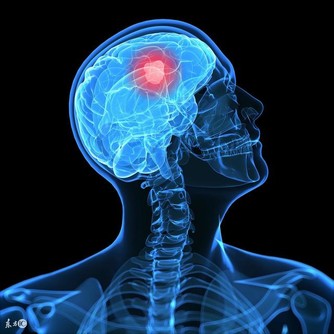

還長了顆水泡,且經常散發出膿液,後來確診王先生罹患了「舌癌」。

舌癌是第一大口腔癌,也被視為「全球第六高發癌症」,